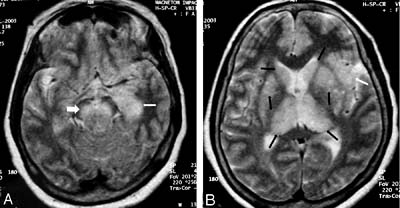

Về giải phẩu bệnh, thông thường các phân tích sau khi đã có kết quả giải phẩu tử thi. Sự biến đổi bệnh lý rõ rệt nhất ở hệ thống thần kinh. Trên kính hiển vi người ta có thể thấy những biến đổi đó là: Phù nề màng não và tổ chức não, các động mạch và tĩnh mạch não dãn rộng và ứ máu, xuất huyết đốm nhỏ ở tổ chức não và màng mềm. Trong tổ chức não và đặc biệt là vùng đồi thị, thể vân và cả sừng amon có những ổ nhũn não và xuất huyết.

Trong các cơ quan nội tạng đều có ứ máu, có nhiều đốm xuất huyết ở niêm mạc và thanh mạc. Thoái hoá tổ chức cơ tim, gan, thận và phát sinh viêm phổi ổ. Viêm xuất huyết và thoái hoá màng não - tuỷ và cả chất não - tuỷ. Ngoài phù nề và xuất huyết đốm ra còn thấy thâm nhiễm quanh các huyết quản của tổ chức não, tủy sống, tạo nên các ổ viêm quanh huyết quản, các ổ quá sản tế bào thần kinh đệm,các ổ hoại tử và nhũn não nhỏ. Những thay đổi bệnh lý nặng nhất xảy ra ở vùng đồi thị, chất xám, nhân đỏ, thể trán và tiểu não.